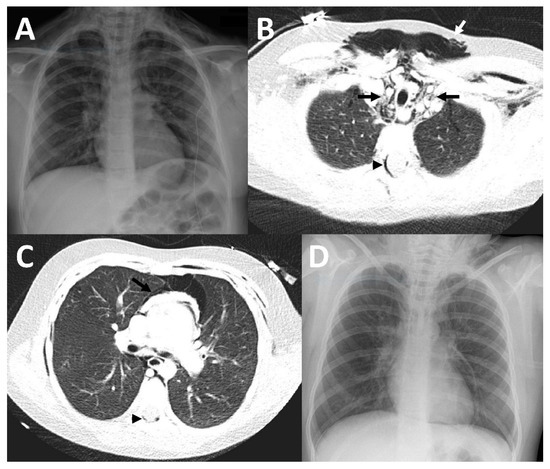

Figure 2.

Imaging findings in patient 2. In the chest x-ray (A), as well as in CT-imaging (B,C) bilateral subcutaneous emphysema (white arrows) and a pneumomediastinum (black arrows) with a Spinnaker sail (angel wing) sign ((A), thymus lobes marked with black arrowheads) was detected. In addition, there were atelectases (white arrowheads), predominantly of the right upper lobe, as well as a pneumothorax (black arrowhead in (B)).